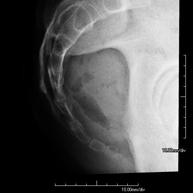

- TMJ X-ray (Temporomandibular Joint)

This technique uses X-ray rendered imaging for examining the temporomandibular joint. Indicated for: trauma, chewing pain, chewing noise, limited mouth opening.